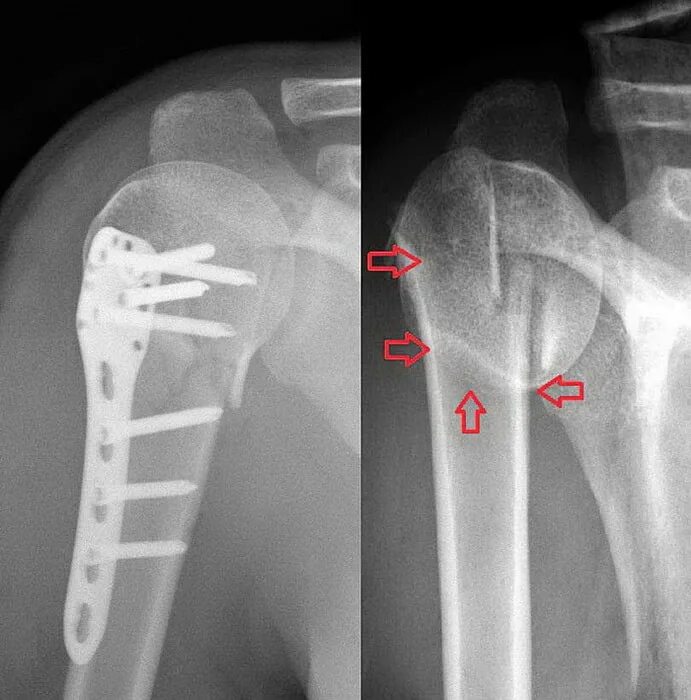

Перелом шейки плеча у пожилых